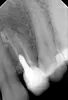

Добрый день, если речь о зубе со штифтом, то его, к сожалению, придется удалить, сломана стенка, когда устанавливали штифт, и воспаление дошло до пика.